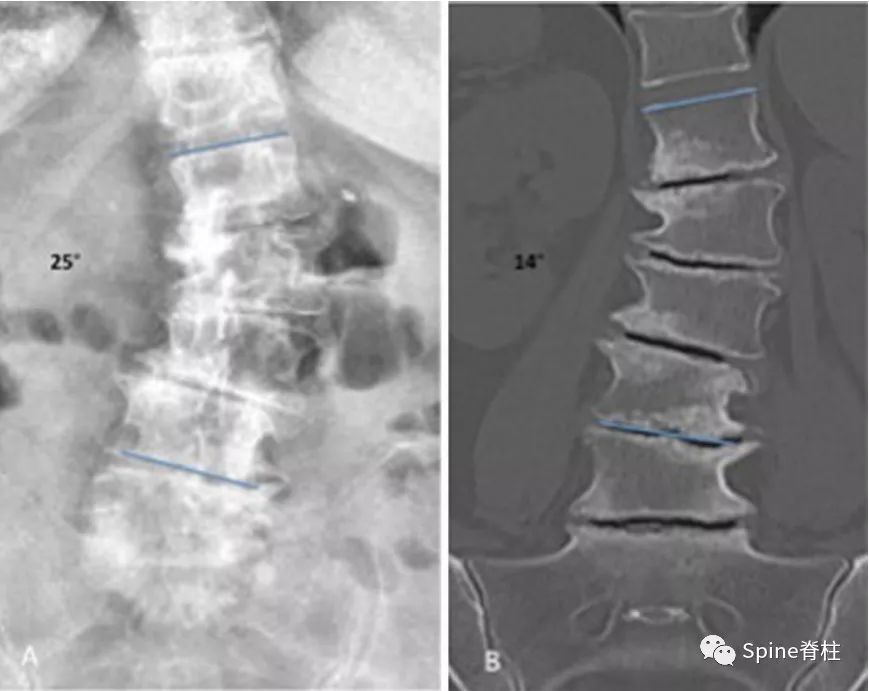

图: 典型的手风琴现象左图为站立位X线片,右图为仰卧位CT。站立位负重时的椎间盘与仰卧位(不负重)椎间盘塌陷程度不同,且侧凸角度也不同(分别为25°和14°)